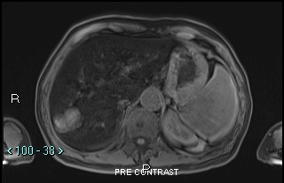

Figure 3A: Non-contrast fat saturated T1 magnetic resonance imaging of the liver with diffuse low signal of hepatic parenchyma from iron deposition. The lesion in segment VII is minimally T1 high signal.

Figure 3B: Magnetic resonance imaging of the liver that shows lobulated mass in segment VII, with mild heterogenous contrast enhancement without significant enhancement in the arterial phase or washout or pseudo capsule on portal venous or delayed phases.

We proceeded with a computed tomography of the liver (CT liver) for further evaluation. CT liver showed a 4.3 x 2.4cm heterogeneously hypodense lobulated mass in segment VII of the liver. The mass was hypodense to the liver on all phases (plain, arterial, venous and delayed). There was mild heterogeneous enhancement, but there was no arterial enhancement (Figure 2A), washout (Figures 2B & 2C) or pseudo capsule, which should be expected in hepatocellular carcinoma. In view of the known history of thalassemia and the presence of paravertebral soft tissue masses that were likely to be extramedullary haematopoiesis, the possibility of extramedullary haematopoiesis was suggested. The other lesion was a 0.9cm hypodensity in segment VI of the liver, which was diagnosed as a flash-filling haemangioma. A magnetic resonance imaging (MRI) was then ordered for the indeterminate segment VII lesion. On MRI, the hepatic segment VII mass in question showed mild heterogeneous contrast enhancement but no appreciable arterial enhancement, washout or pseudo capsule (Figure 3A & Figure 3B).

The lesion remained indeterminate due to the absence of typical features for hepatocellular carcinoma. Extramedullary haematopoiesis remained a possibility and a tc-99m sulphur-colloid scan was suggested for further characterisation. On MRI, the liver also showed marked low signal on T1 and T2 as well a gain in signal on the in-phase T1 scan. These findings were compatible with hepatic hemosiderosis. MRI also confirmed that the smaller lesion in segment VI was a flash-filling haemangioma.